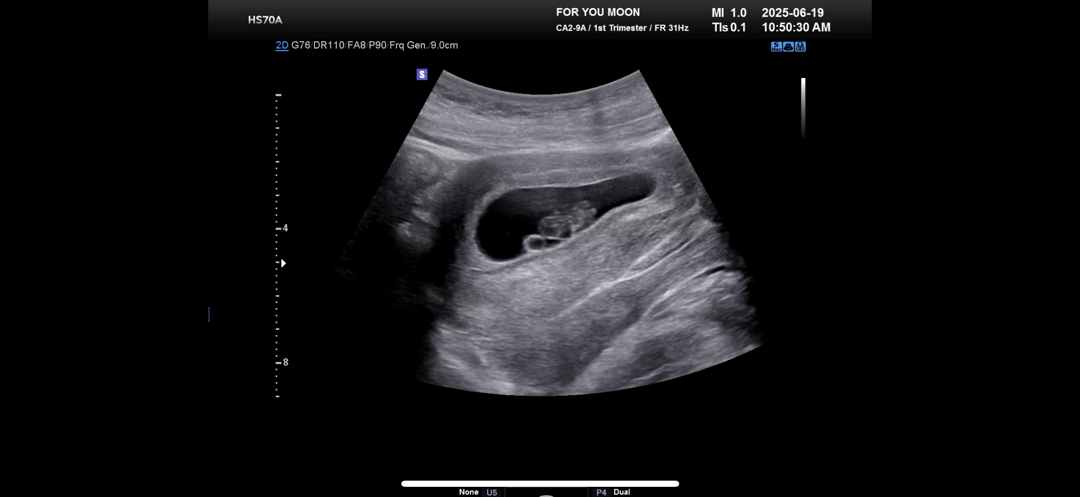

8주2일차 초음파 보고왔어용

상상했던 젤리곰 모양은 아니지만 그래도 귀엽.. 초음파 잘 보여주시는 선생님들 부러워요ㅠㅠ 서브병원을 알아봐야 할까봐욬ㅋㅋㅋㅋ